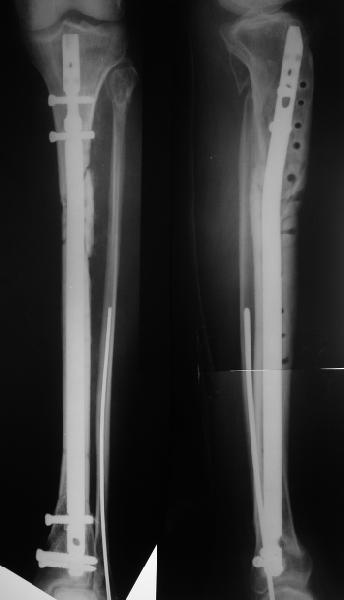

Alexander Chelnokov 26 Июнь 2004, 01:07

Еще раз спасибо! Сделали вчера. Все прошло по плану, интраоперационное фото после удаления пластинки и итоговые снимки прилагаю. Гвоздь бесканальный 12 мм. Сегодня пациентка уже ходит по палате с одним костылем.